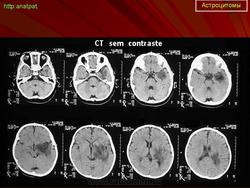

ГМ. Астроцитома. +

Астроцитома.